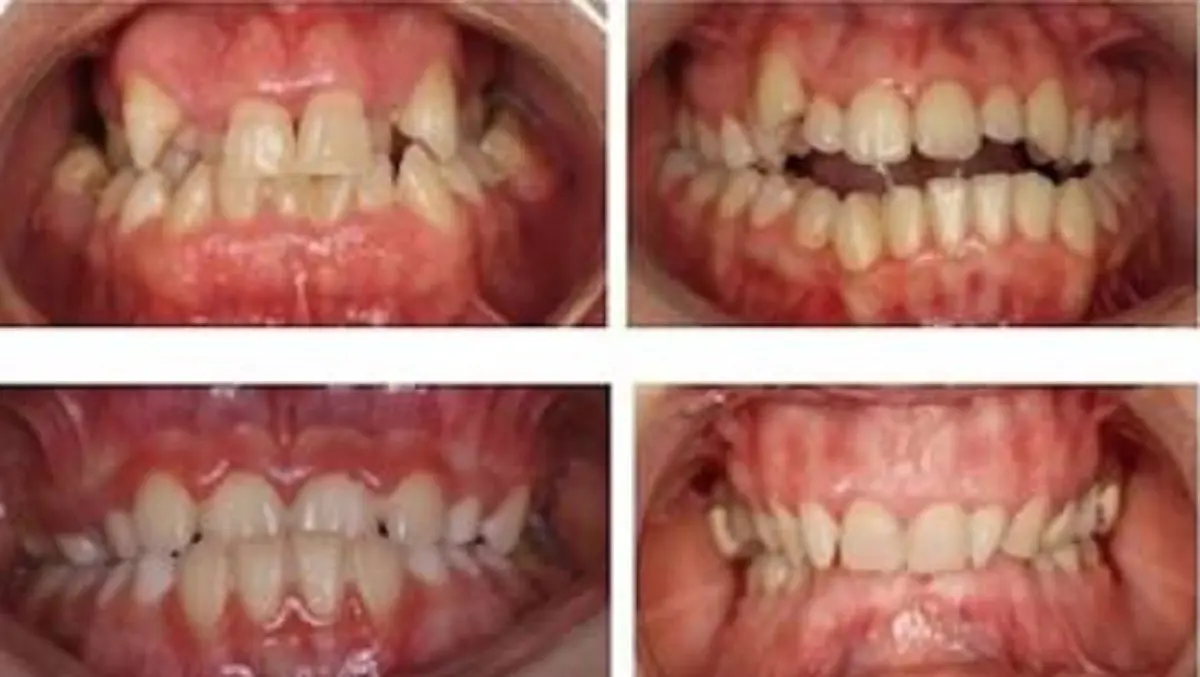

De acuerdo a la doctora Lucía Rodríguez Fonseca, la cirugía ortognática es un procedimiento habitual y la planificación 3D permite al ortodoncista y al cirujano maxilofacial un correcto diagnóstico y resultados predecibles. «Es imprescindible que el ortodoncista y el cirujano maxilofacial analicen el caso de forma conjunta, para diseñar la fase de ortodoncia pre-quirúrgica. Esta fase, consiste en corregir todas las compensaciones dentarias existentes, colocando los dientes en su base ósea y proporcionando al cirujano una estructura estable y correcta de ambas arcadas para llevar a cabo los movimientos esqueléticos planificados», destaca la doctora.

El trabajo de corrección se realizará aplicando las principales técnicas quirúrgicas. La cirugía del maxilar superior, «que permite el avance, desplazamiento vertical del maxilar superior y/o rotación del mismo. Se utiliza para la corrección de los casos de Clase III o prognatismo mandibular, mordidas abiertas o sonrisas gingivales. La cirugía de la mandíbula, que permite el avance o retroceso mandibular, siendo el avance mandibular la técnica más practicada en mandíbula. Se utiliza en la corrección de la Clase II o retrognatia».

La Cirugía maxilo-manbibular o cirugía ortognática bi-maxilar, – continua la especialista del Hospital La Luz -, se utiliza en aquellos casos donde es necesario reposicionar tanto el maxilar, como la mandíbula, para lograr una correcta oclusión y estética facial. Se utiliza para el tratamiento de las Clase II, Clase III y asimetrías mandibulares.

Tras la intervención, se continúa con la fase de ortodoncia post-quirúrgica, «con el fin de estabilizar la nueva posición quirúrgica y facilitar una guía funcional a la nueva relación de los maxilares», concluye la doctora.